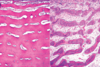

Distinct groups of atrophic and hypertrophic fibres in child w/ spinal muscular atrophy, hypertrophic fibres up to 100 micrometres

Atrophy restricted to darkly stained type 2 fibres induced by steroid therapy

ATPase staining following preincubation at pH 4.3 showing atrophy selectively affecting darkly stained type 1 fibres in a case of myotubular myopathy + hypertrophy of pale type 2 fibres